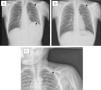

Radiografía de tórax: A) Derrame pleural subpulmonar (elevación del supuesto hemidiafragma izquierdo con aumento de la distancia entre el «hemidiafragma» y la cámara gástrica con desplazamiento lateral de la cúpula del seudodiafragma izquierdo), así como ausencia de clavícula izquierda (flechas). B) Después de la toracocentesis evacuadora. C) En la radiografía obtenida unos 6 meses antes se puede observar la clavícula en proceso de reabsorción. Esta imagen llevó al diagnóstico erróneo de seudoartrosis.

En enero de 2015, es remitido por traumatología para estudio de un derrame pleural aparecido en un estudio radiográfico de control. Se realiza una toracocentesis diagnóstica y evacuadora que resulta un exudado monocitario con citología y bacteriología negativas, destacando en la bioquímica unos triglicéridos de 143mg/dl. Por el quilotórax, la osteólisis de clavícula y los datos patológicos en la biopsia de la misma se diagnosticó de síndrome de Gorham-Stout (Fig. 1). Sigue actualmente tratamiento con dieta, bifosfonatos y peginterferón alfa-2, sin nuevos focos osteolíticos ni progresión de los previos, aunque con recidiva del quilotórax.